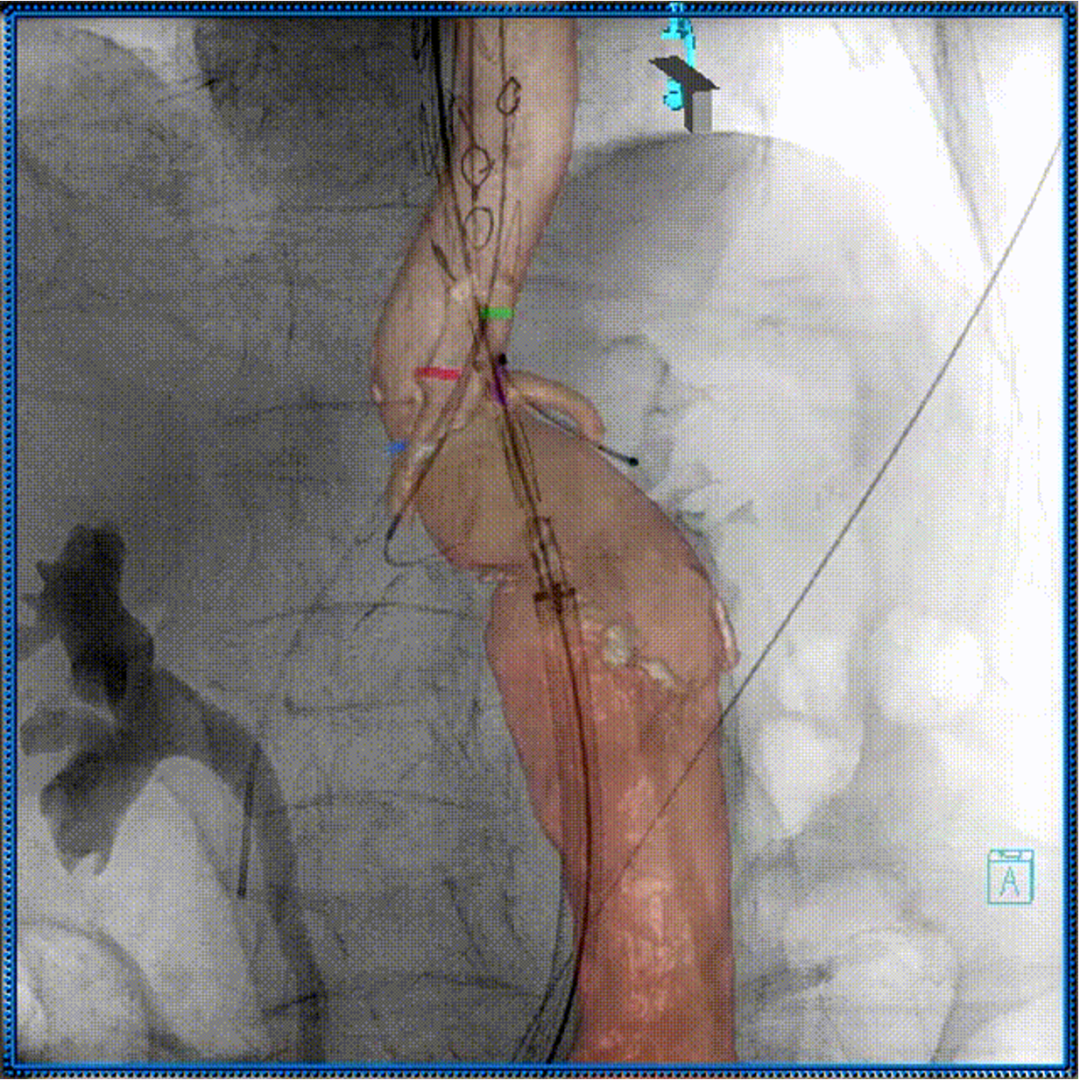

3D影像引导下完成窗口超选、置管及确认

肠系膜上动脉重建

左肾动脉重建

右肾动脉重建

四分支重建后造影,各分支血流通畅